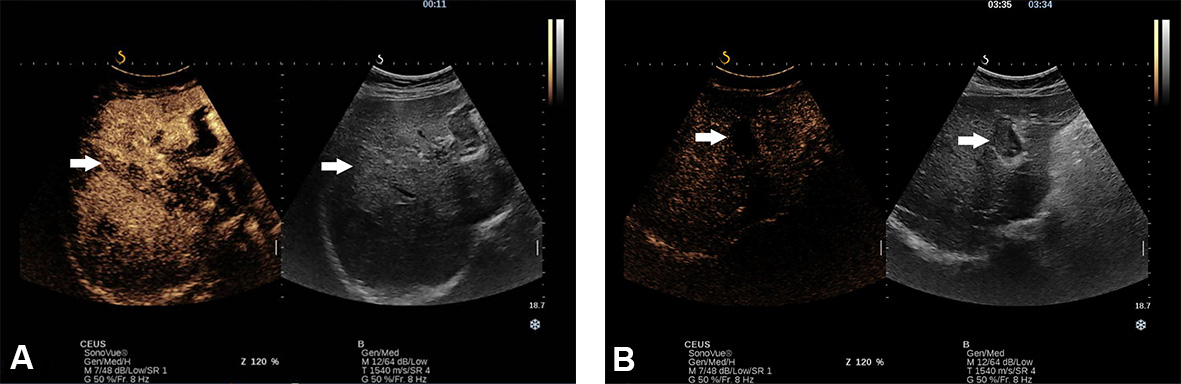

Another aspect that must be considered is the infiltrative pattern of HCC associated with an increased risk of surveillance failure compared to the nodular type (57.1% vs. 2.1%; P < 0.001)[28]. Noteworthy, advanced HCC may coexist with a macrovascular invasion. Based on the thrombus echogenicity, US cannot differentiate between malignant and benign thrombus. Even though Colour Doppler can detect the presence of vessels, indicating malignity, the method’s sensitivity is lower than 20%[29] [Figure 4A and B]. Thus, US visualisation of macrovascular thrombosis requires further imaging with contrast agents.

Figure 4. Thrombosis of portal vein (main, right and left branch) in a 62-year-old man recently diagnosed with NASH-related cirrhosis in B mode (A) and Doppler mode (B).